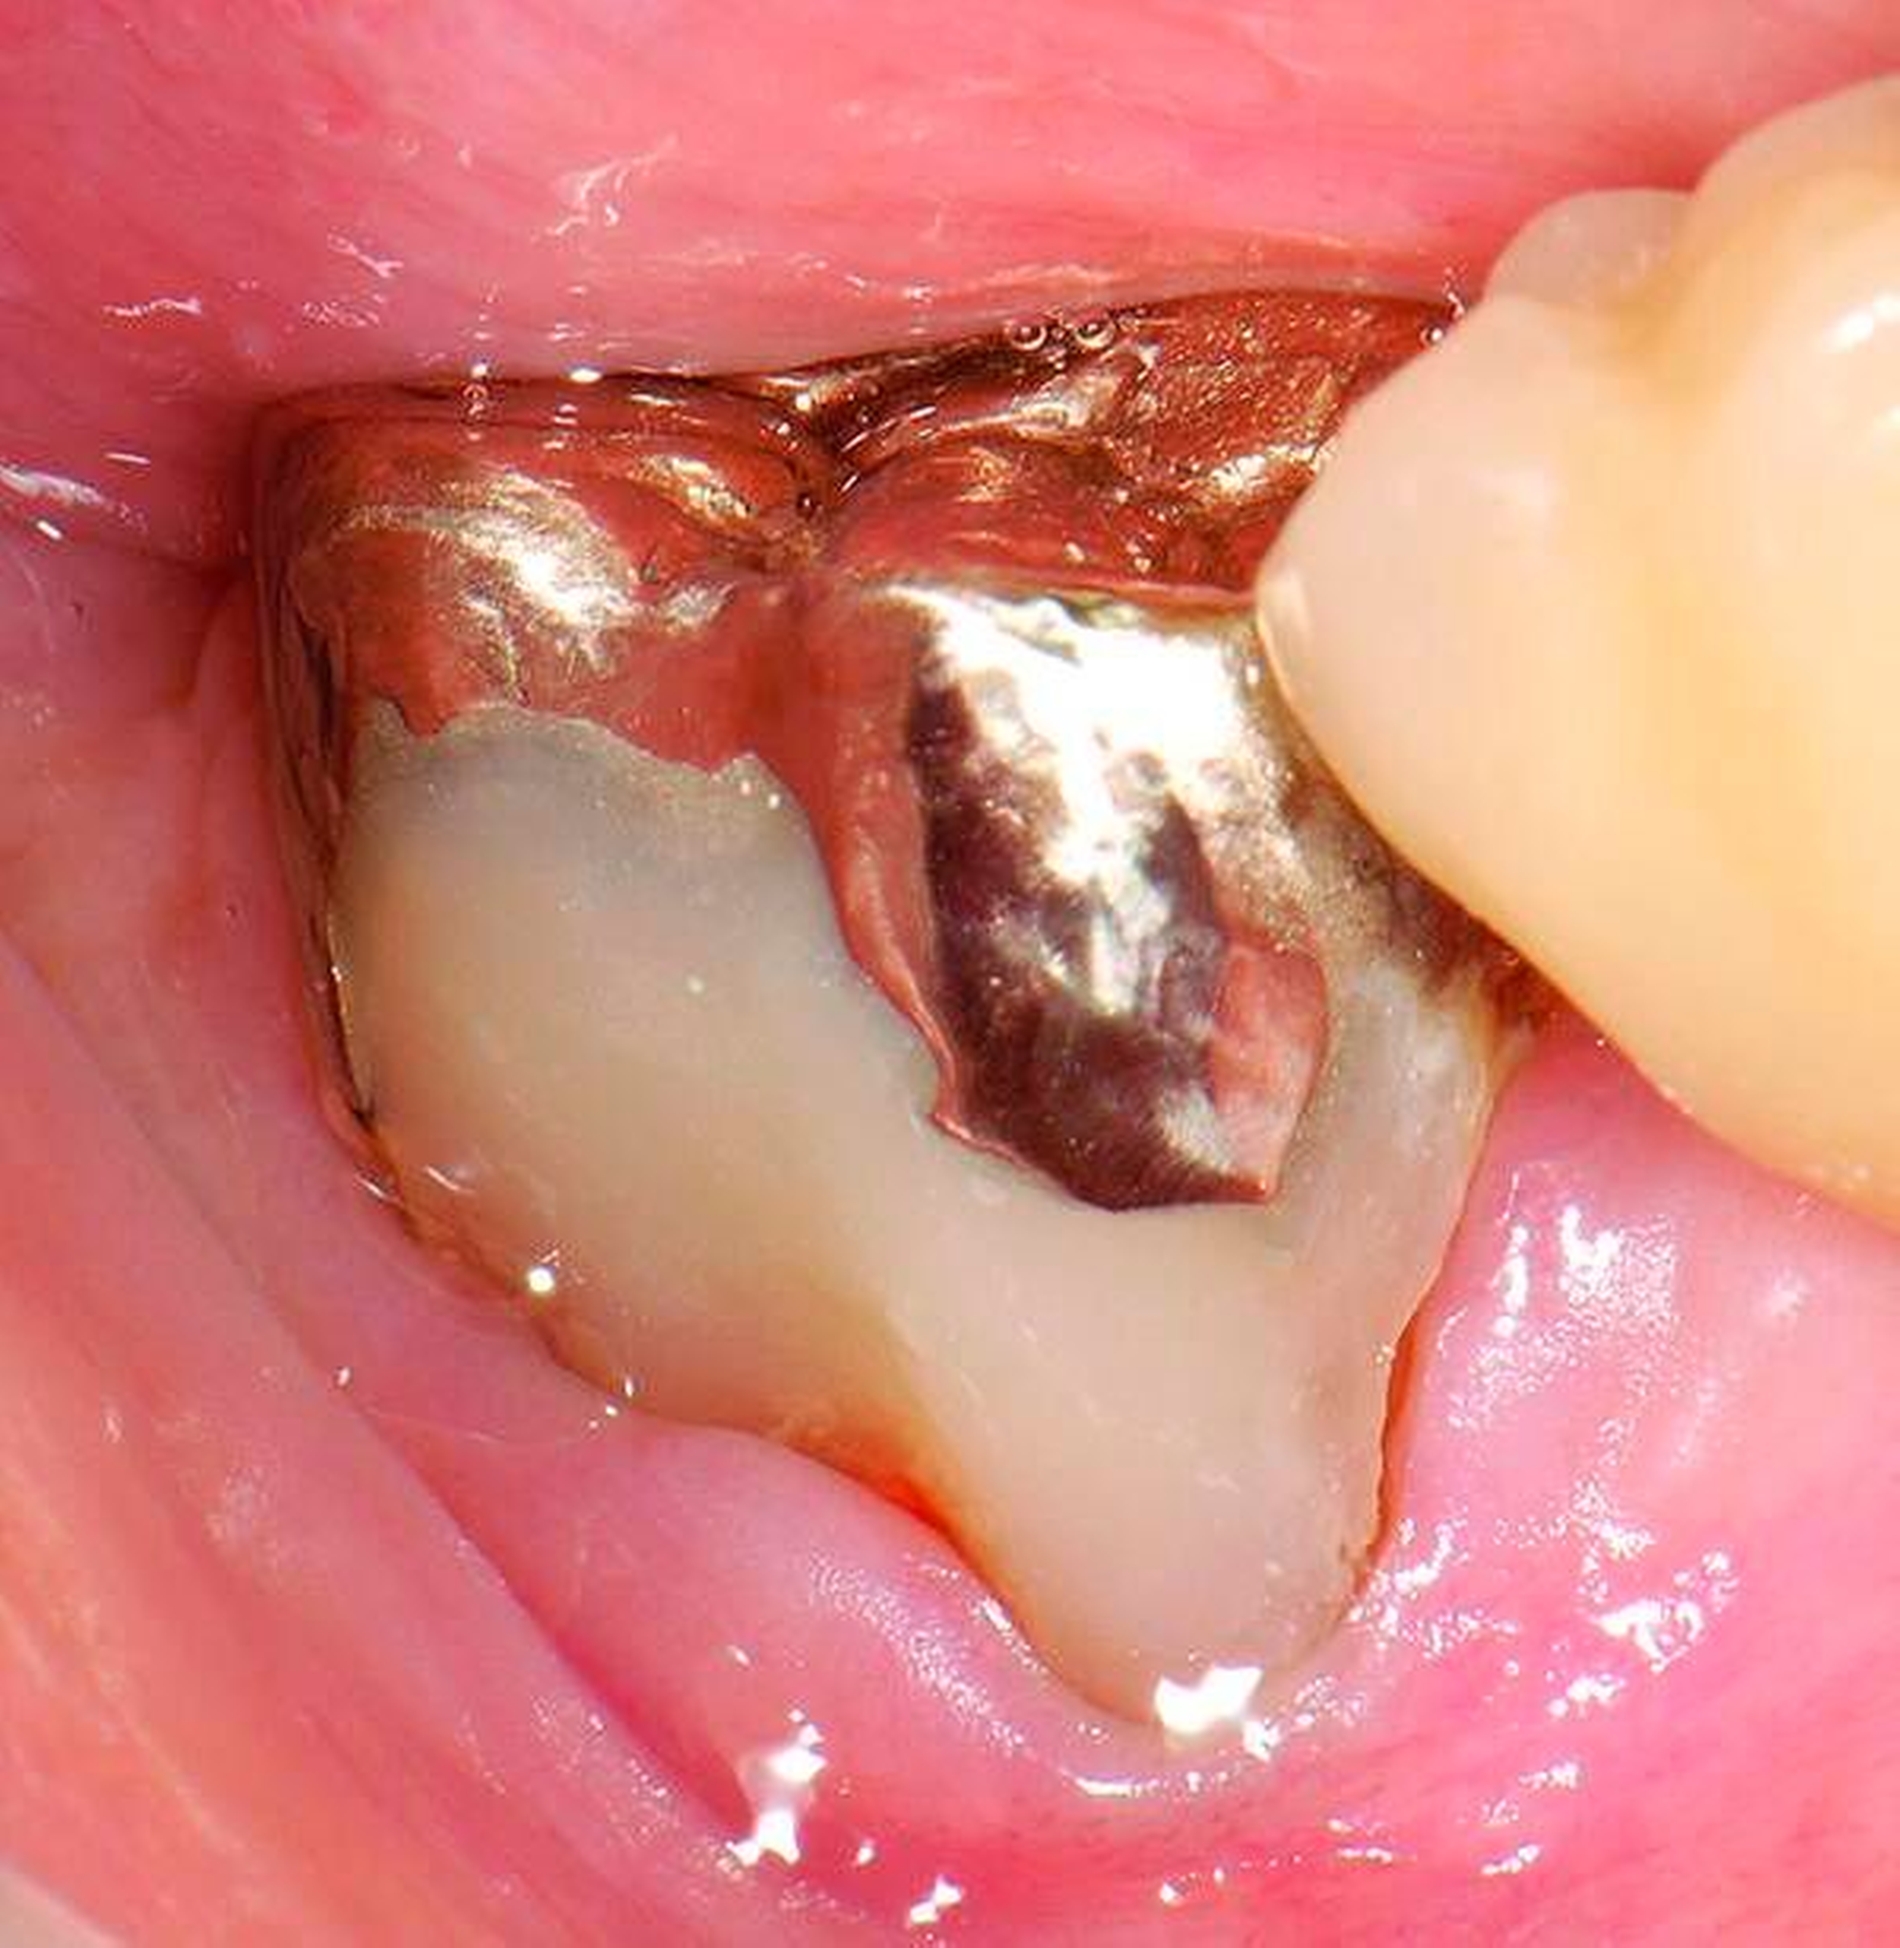

4. Vorgehen bei frakturierten Zahnkronen/Wurzelresten

Üblicherweise werden frakturierte Zahnkronen beziehungsweise Wurzelreste restaurativ wieder aufgebaut oder es erfolgt eine Extraktion. Im Seniorenalter erscheint es hingegen manchmal als Kompromissmaßnahme vertretbar, Wurzelreste vorerst zu belassen und etwa mit adhäsiv eingebrachtem Komposit knapp über Gingivahöhe abzudecken. Dies bietet sich vor allem dann an, wenn die Wurzelkanäle bereits obliteriert und endodontische Interventionen nicht erforderlich sind (Tabelle 4) [Staehle et al., 2017].

Abbildung 4: Anliegen eines 76,5-jährigen Patienten (Anfrage per E-Mail). Zitat: „Mich plagt eine … Entzündung des Mundraums, die auch das Zahnfleisch meiner Zahnstummel angreift, weshalb ich nur noch Breiartiges zu essen vermag. Ein Angsthase wie ich geht zum Zahnarzt NUR unter dem Eindruck akuter Schmerzen!“

Damit wird die Hygienefähigkeit zumindest partiell verbessert und Spielraum für künftige Planungen und Vorgehensweisen unter besseren Bedingungen belassen. Das Procedere ist in den Abbildungen 4 und 5 beschrieben. Bei dem in Abbildung 4 vorgestellten Patienten lag eine Oralphobie im Seniorenalter vor. Die Verlaufsbeschreibung macht deutlich, dass selbst im fortgeschrittenen Alter eine Adaptation an zahnärztliche Interventionen im Einzelfall noch möglich ist.